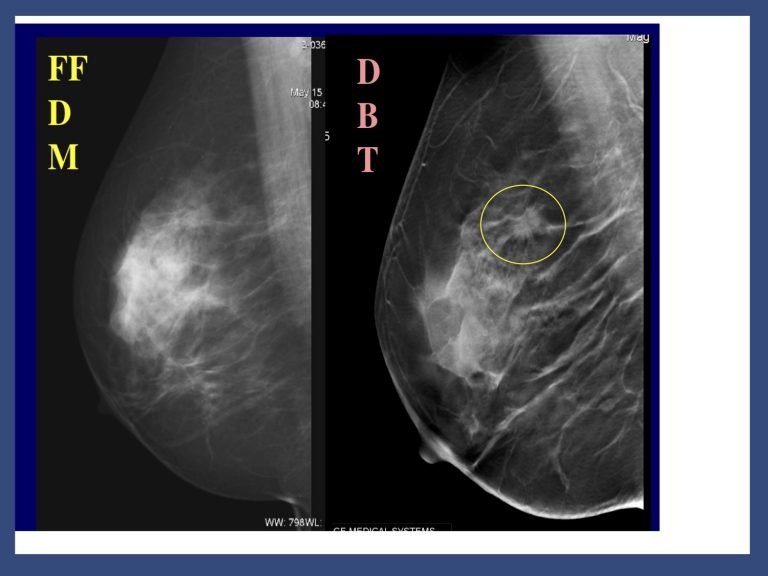

Vi sono ormai consolidate evidenze che la mammografia 3D (tomosintesi) sia più sensibile della mammografia digitale tradizionale. Non solo migliore sensibilità ma anche maggiore specificità.

La tomosintesi è tecnica più sensibile della mammografia 2D perché ottimizza i vari aspetti menzionati. L’impianto mammografico viene modificato per consentire alla sorgente radiogena di ruotare ed eseguire radiografie del seno a diversi angoli di proiezione; le immagini digitali, acquisite a bassa dose, sono poi opportunamente combinate per ricostruire le sezioni a diversa profondità. La tomosintesi in pratica è una mammografia migliore. Nata per superare i limiti della mammografia digitale 2D la tomosintesi permette di ricostruire una stratigrafia della mammella a partire da un numero finito di proiezioni bidimensionali. Di ultimissimo sviluppo è il CAD che mediante marker segnala le aree di maggiore interesse.

Ciò contribuisce a ridurre gli artefatti da sovrapposizione o sommazione e ad ovviare al mascheramento delle lesioni relativo alla densità mammaria. La tomosintesi è in grado di visualizzare separatamente oggetti posti a profondità diverse tramite l’acquisizione di molteplici proiezioni bidimensionali a bassa dose per diverse angolazioni del tubo rx intorno alla mammella con detettore fermo. I dati acquisiti vengono ricostruiti in una serie di strati sottili ad alta risoluzione.

La ricostruzione 3D supera i limiti della Mammografia 2D dovuti a densità mammaria e sovrapposizione dei tessuti che determinano mascheramento e misconoscimento dei tumori.